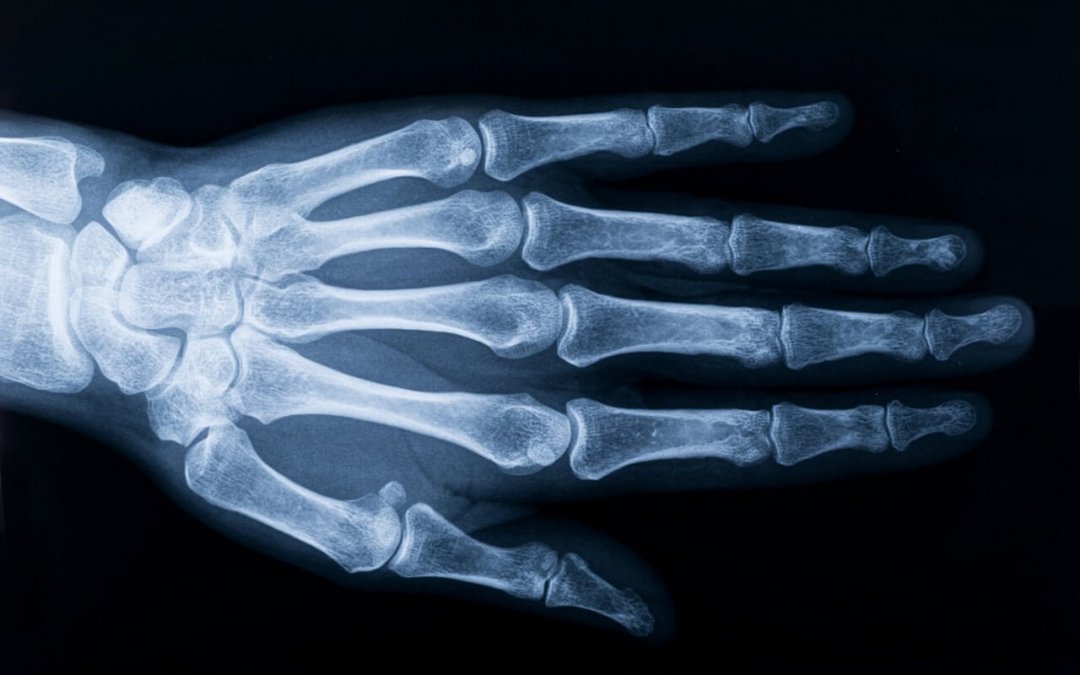

Osteoartrite (OA) tem sido considerada uma doença “tipo desgaste” que conduz à perda de cartilagem. OA costumava ser considerada a única consequência de qualquer processo que conduzisse ao aumento da pressão em uma determinada junta ou a fragilidade da cartilagem matriz. Avanços da biologia molecular na década de 1990 modificaram profundamente este paradigma. A descoberta de que vários mediadores solúveis, tais como citoquinas ou prostaglandinas podem aumentar a produção de matrizes  metaloproteinases pelos condrócitos, conduziu aos primeiros passos de uma teoria “inflamatória”. No entanto, levou uma década antes que a sinovite fosse aceita como um padrão crítico da OA; e alguns estudos estão abrindo caminho para considerar a condição como um condutor de processo da OA.

Dados experimentais recentes têm mostrado que o osso subcondral pode ter um papel substancial no processo de OA, como um amortecedor mecânico, bem como uma fonte de mediadores inflamatório envolvidos no processo de dor da OA e na degradação da camada profunda da cartilagem. Assim, inicialmente considerado cartilagem danificada, a OA é uma doença muito mais complexa; com mediadores inflamatórios liberados pelo osso, cartilagem e membrana sinovial. Baixo grau de inflamação induzida pela síndrome metabólica, imunidade inata e inflammaging (*), são alguns dos argumentos mais recentes em favor da teoria inflamatória da OA e destacadas nesta revisão.